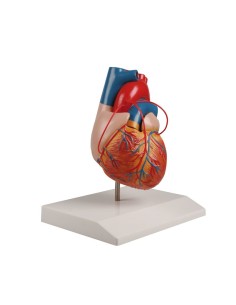

Dal cranio in 22 parti con incastri magnetici ai modelli di colonna vertebrale, da quelli di articolazioni a quelli di cuore, ogni pezzo della nostra collezione è progettato per un’immersione totale nello studio dell’anatomia umana. I nostri modelli, realizzati tramite scansioni di ossa vere, garantiscono un’esperienza tattile autentica e una fedeltà di peso quasi identica agli originali.

Essenziali per studenti e professionisti, i nostri modelli anatomici sono strumenti didattici che permettono di osservare le strutture anatomiche con precisione, eliminando la necessità di dissezioni o studi invasivi. Sono inoltre utili per spiegare ai pazienti le patologie, rendendo la comunicazione più efficace e risparmiando tempo prezioso.